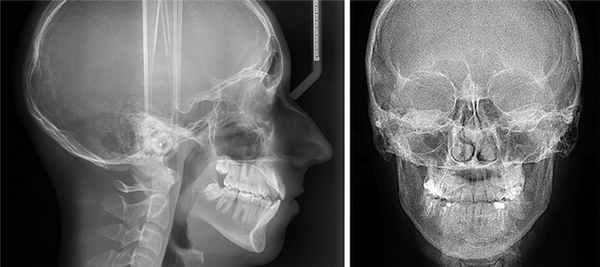

Телерентгенограмма (ТРГ)

Этот вид диагностики позволяет исследовать не только челюстную структуру, но и получить снимок всего черепа в фас и профиль. Относится к числу наиболее информативных диагностических процедур в стоматологии.

ТРГ проводится в обязательном порядке перед установкой брекет-систем, а также широко используется перед предстоящими операциями в качестве подготовительной меры.

Ортопантомограмма (ОПТГ)

Это один видов исследования, пользующийся достаточным спросом. С помощью данной методики удается получить изображение абсолютно всех челюстей и зубов.

Что дает панорамный снимок зубов?

Полученное изображение дает специалисту следующие сведения:

- Наличие фибром и других новообразований.

- Скрытый кариес.

- Выявить непрорезавшиеся зубы и их точное положение.

- Выявить костные заболевания.

Другими показаниями к ОПТГ являются предстоящая процедура имплантации, запланированное хирургическое вмешательство, а также другие сложные манипуляции.